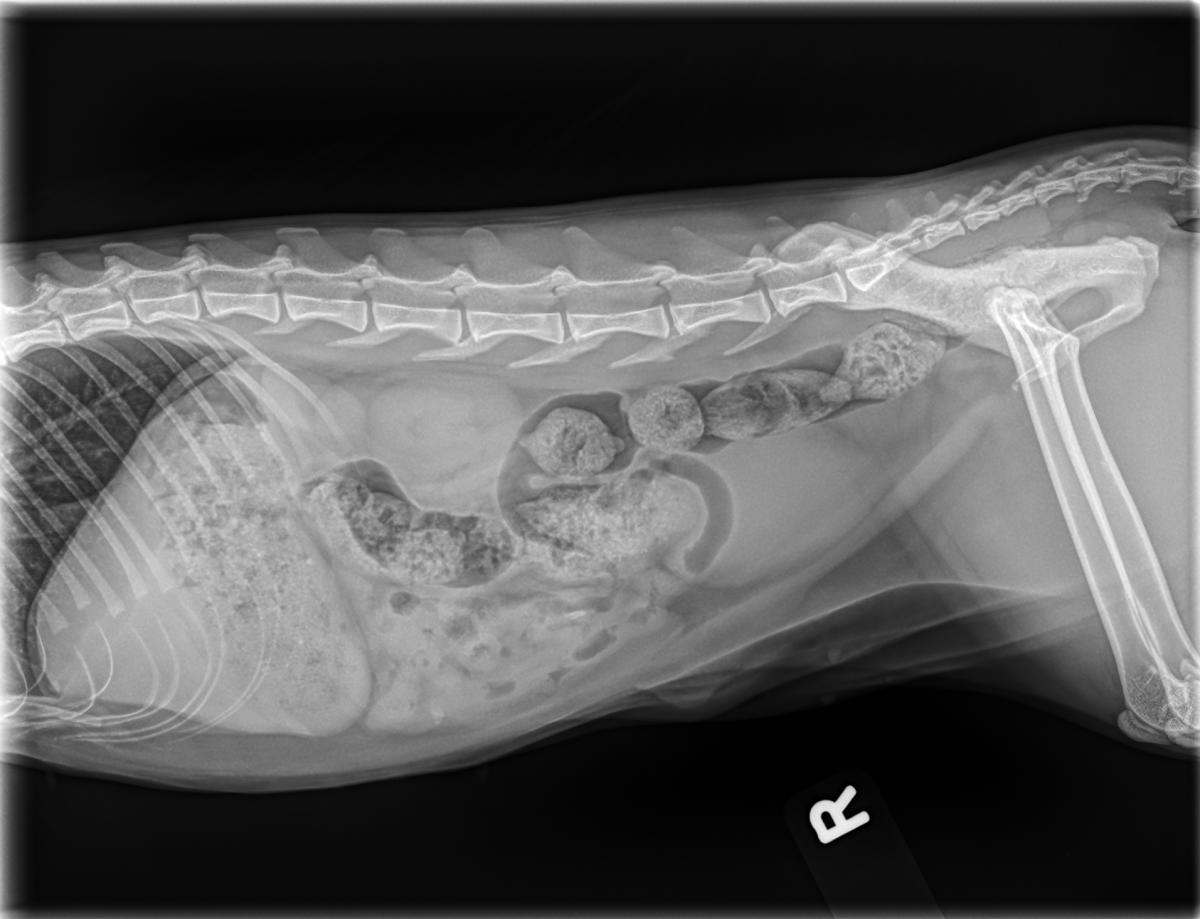

Digital X-Rays

We have two digital X-ray systems: A full-size digital X-ray unit for evaluating the chest, abdomen, bones, and joints. As well as a dedicated dental X-ray unit, which allows us to assess tooth roots and underlying bone (areas that cannot be seen during a routine dental exam).

All X-rays are digital, which means: faster image capture, excellent image quality, immediately available for review and upload to your pet’s medical record, as well as easy sharing with specialists when needed.

When cases require additional expertise, we can consult with a board-certified veterinary radiologist for expert review and interpretation of images.